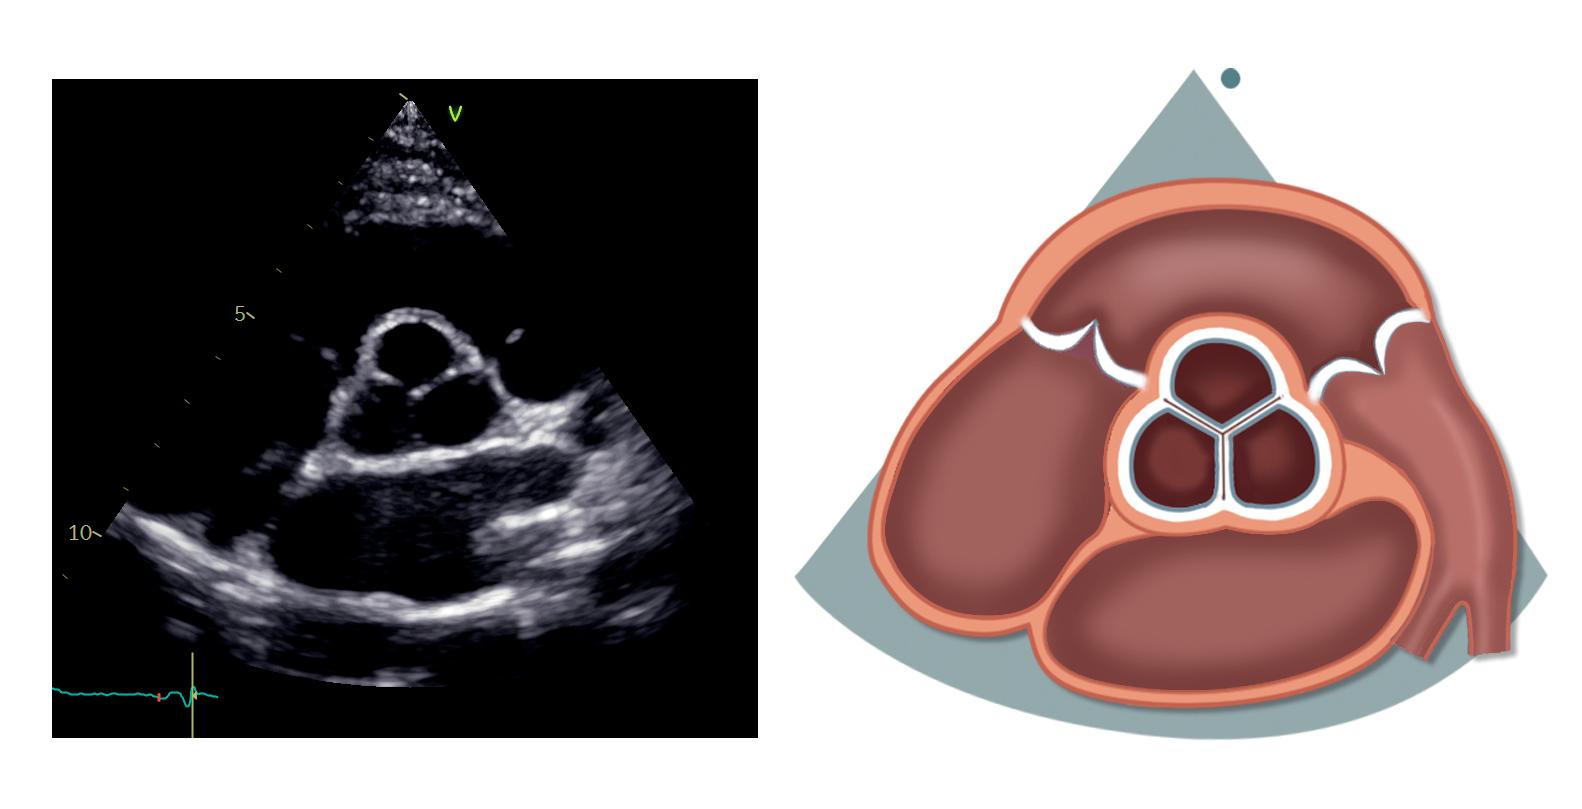

Parasternal kortakseprojeksjon

– aortaklaffnivå

Fra parasternal langakseprojeksjon roterer vi transduseren 90 grader med klokken slik at markøren peker mot pasientens venstre skulder. Vi kommer da til parasternal kortakseprojeksjon på aortaklaffnivå (figur 2.3).

Trikuspidalkla en (TK)

Pulmonalkla en (PK)

Aortakla en (AK)

Truncus pulmonalis (TP)

Venstre arteria pulmonalis (VAP)

Høyre arteria pulmonalis (HAP)

Ved å vinkle og reposisjonere transduseren med utgangspunkt i denne projeksjonen kan vi skanne gjennom hele venstre ventrikkel fra basis til apex.

I aortaklaffnivå ses aortaklaffen i kortakse sentralt i bildet. Klaffens tre kusper fremstilles med den non-koronare kuspen mot atrieseptum, den høyre koronare kuspen nærmest RVOT (høyre kusp grenser kun mot høyresidige hjertekamre) og den venstre koronare kuspen på venstre side (mot truncus pulmonalis og venstre aurikkel).

Dersom vi vinkler transduseren litt anteriort og innsynet er godt, kan ostiene til koronarkarene noen ganger komme frem der de utgår fra aortaroten. Venstre hovedstamme ses vanligvis klokken 4, mens høyre koronararterie ses klokken 11–12. Her er det imid-

lertid noe variasjon, både i rotasjonen av aortaroten og i anatomien til koronararteriene.

RVOT ligger over aortaklaffen på bildet, mens pulmonalklaffen ligger over og til høyre. Truncus pulmonalis ses til høyre, og noen ganger får vi også frem bifurkaturen, høyre og venstre lungearterie. Til venstre ses trikuspidalklaffen med det septale og fremre (eventuelt bakre) seilet. Litt avhengig av transduserposisjon kan noen ganger alle tre seil visualiseres samtidig – det septale inn mot aortaroten til høyre, det bakre muralt til venstre, mens fremre seil kommer frem i midten. Begge atriene og atrieseptum ligger under aortaklaffen, og hos noen kan deler av venstre aurikkel ses til høyre på bildet.

Tabell 2.3: Sentrale målinger i parasternal langakseprojeksjon –høyre ventrikkels utløp Figur 2.3: Parasternal kortakseprojeksjon – aortaklaffnivå Atrieseptum (IAS) Høyre atrium (HA) Venstre atrium (VA) RVOT RVOT TK HA PK AK TP VA IAS

Tabell 2.4 lister opp sentrale målinger i parasternal kortakseprojeksjon – aortaklaffnivå.

Tabell 2.4: Sentrale målinger i parasternal kortakseprojeksjon –aortaklaffnivå

Målinger i parasternal kortakseprojeksjon – aortaklaffnivå

Proksimale RVOT (endediastolisk) og distale RVOT (midtsystolisk)

Lungearteriens

diameter (endediastolisk)

Pulset doppler i RVOT (målevolumet plassert 5–10 mm proksimalt for pulmonalklaffen)

Kontinuerlig doppler over pulmonalklaffen